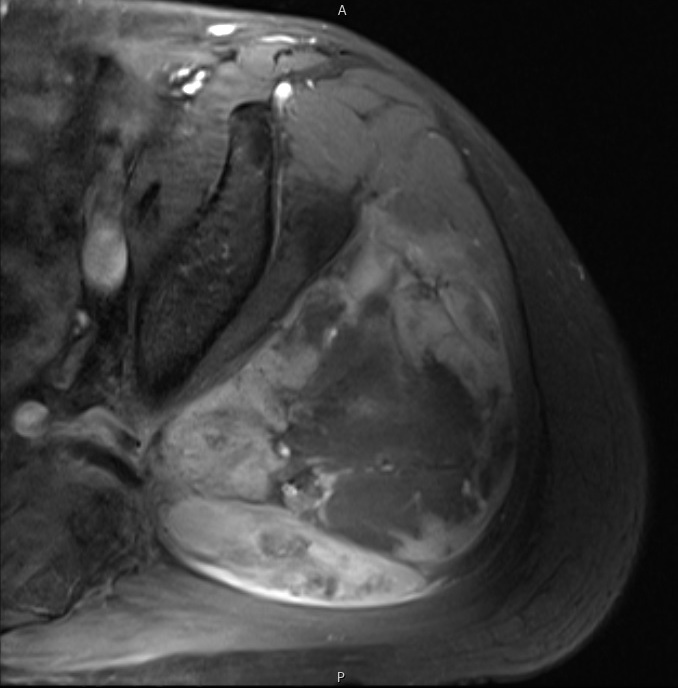

Axial (Fig. 4) and Coronal (Fig. 5) contrasted T1-weighted MR images show a large heterogeneous mass with central and peripheral enhancement. Central low signal intensity image is compatible with necrosis and hemorrhage.

Fig. 6 STIR MR image demonstrates a large mass in the gluteal region with some enhancing tissue posterior to the trochanteric area which may reflect reactive edema.